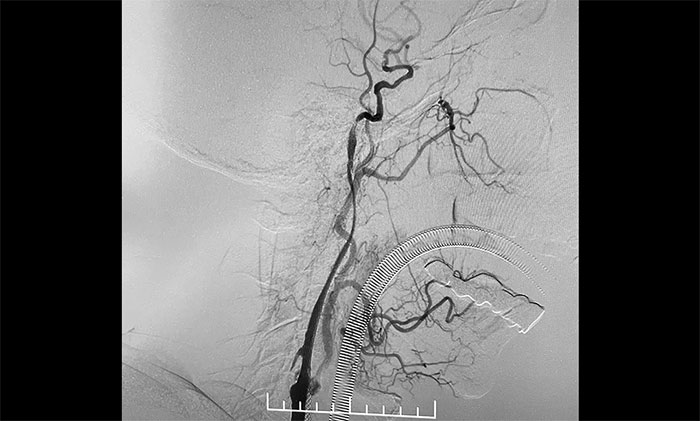

▲ 左侧颈内动脉闭塞顺利开通

术中,超滑导丝、多功能导管经过反复尝试顺利通过左颈内动脉起始段,到达左颈内动脉远端显影段,路图见远端血管通畅,左大脑中动脉显影;随后,微导丝经多功能导管置于左颈内动脉海绵窦段,经微导丝送入保护伞至左颈内动脉岩骨垂直段并释放,再沿保护伞微导丝送入4x30mm球囊于左颈内动脉起始段,给予球囊扩张,撤除球囊后造影见左颈内动脉起始段再通,左颈内动脉、左大脑中动脉显影;最后,送入9x50mm支架,释放于左颈内动脉颈段至左颈总动脉末段,造影见左颈内动脉起始段显影明显改善,左颈内动脉、左大脑中动脉、左大脑前动脉显影可,行3D造影见左颈内动脉颈段显影改善。行支架CT见支架成形可,行XperCT未见颅内出血。

手术圆满完成,席刚明教授团队、麻醉科团队及导管室团队通力合作,耐心、仔细地克服了手术的所有难点。左颈内动脉从“无”到“有”,正所谓“精诚所至,金石为开”,顺利为患者解除危机。